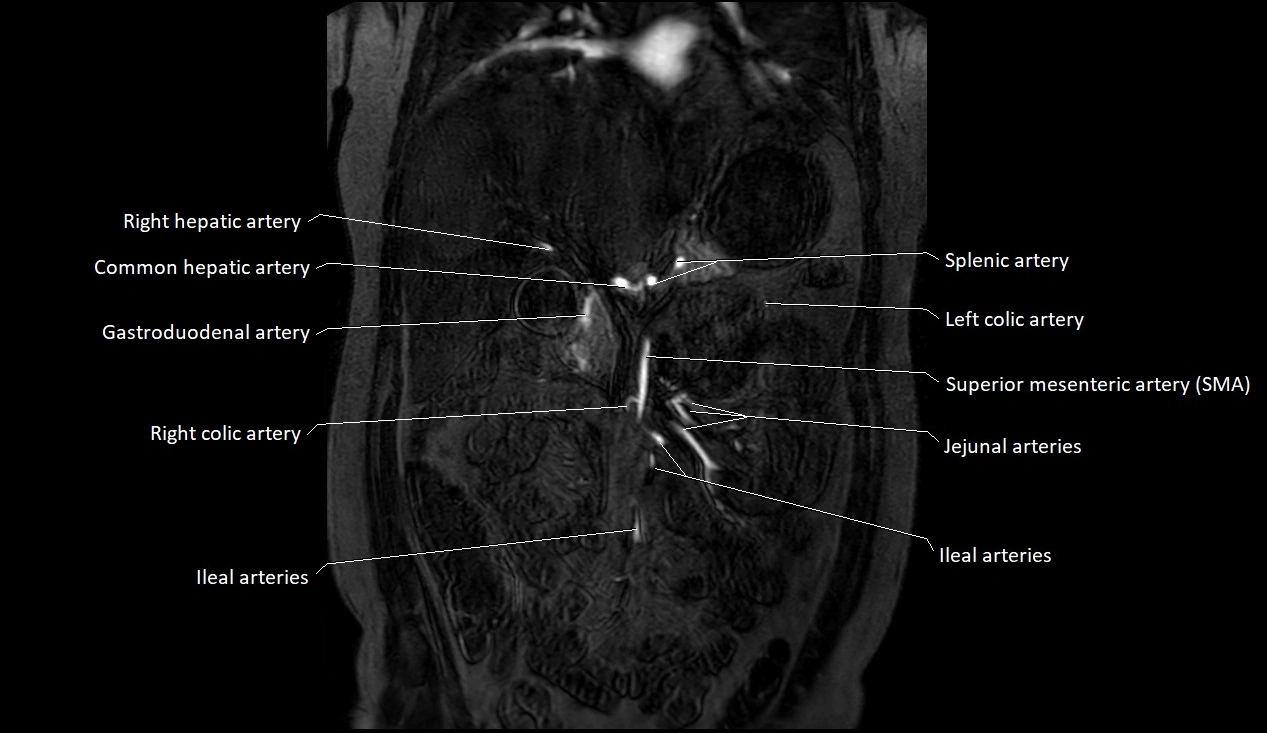

MRA (Magnetic Resonance Angiography):

• Contrast-enhanced MRA provides high-resolution imaging of the aorta and its branches

• Allows 3D reconstruction of visceral, parietal, and terminal branches

• Excellent for evaluating aneurysm size, dissection flap, stenosis, or preoperative planning

• Non-invasive alternative to conventional angiography

MRI images

image